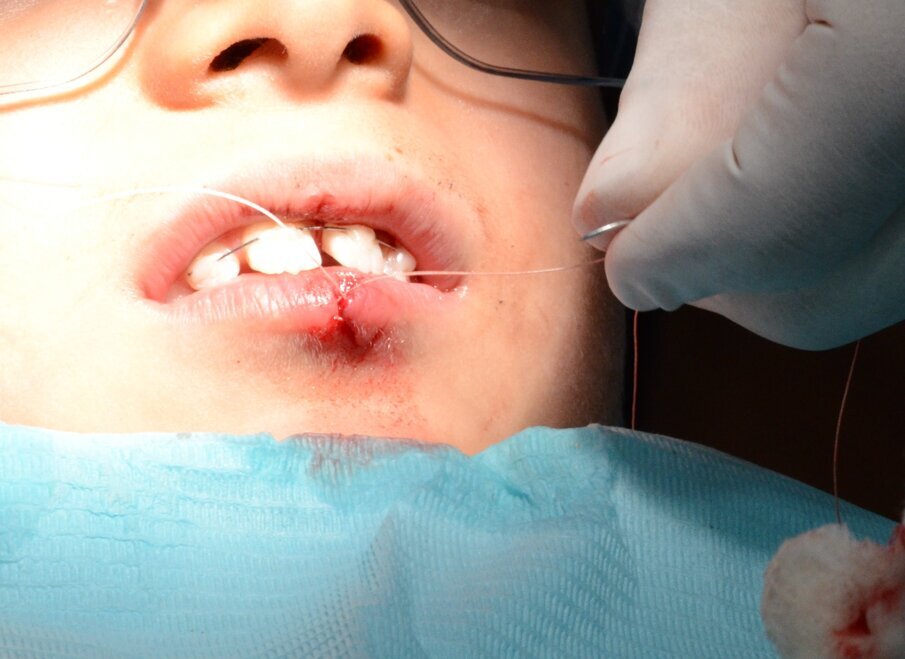

An 8-year old child presented to the department of paediatric dentistry at the Hamdan Bin Mohammed College of Dental Medicine (HBMCDM) at the Mohammed Bin Rashid University (MBRU) in Dubai Healthcare City. He allegedly fell off a climbing wall, and knocked out his upper left maxillary incisor (tooth # 21) and cut his lower lip (Figures 1 and 2). This occurred at 14:15 hours at school, and the school nurse called the patient’s mother at 14:20 hours. The patient’s mother asked the nurse to find the tooth and put it in milk. The tooth’s “dry time” was thus around 10 minutes. The patient attended with both his mother and aunt, to our specialist clinic at 14:55 hours.

• Lower lip through- and-through ragged laceration of the lower lip (Figure 1).

Within the hour, tooth 21 was gently replanted into the socket (Figure 6) and a flexible 0.5mm wire/composite passive splint of teeth #12, 11, 21, 22 was secured (Figure 7). We sutured the lacerated lower lip in multiple layers (mucosa, deep and superficial) using Vicryl® (Sizes 40 and 60) resorbable fine sutures (Figure 8 and 9). This took place after thorough debridement of the wound with physiological saline. Care was taken to assure alignment of the lip’s vermilion involved in the laceration.

Figure 1: Initial presentation. 21 was avulsed and its socket appeared empty. There was a laceration of the lower lip

Figure 8. Suturing of the lower lip laceration in three layers using fine resorbable sutures (Vicryl® Sizes 40 and 60).

Figure 9. Immediate post suturing. Notice the wound margins had been aligned so the vermilion was continuous.